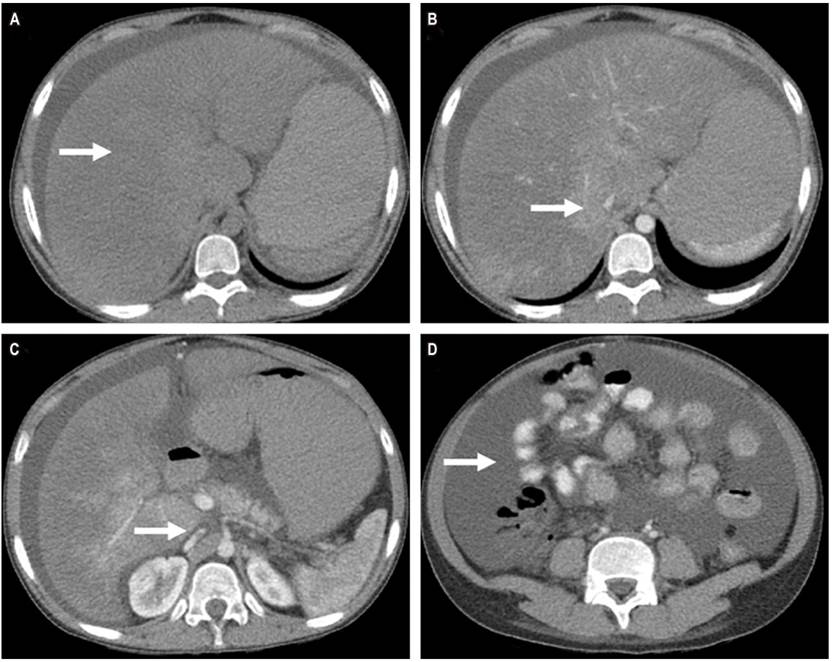

Se trata de una paciente de 14 años, de raza negra, procedente del área urbana de Quibdó, Chocó, quien tiene historia de parto vértice espontáneo a término sin complicaciones y anticoncepción posparto con acetato de medroxiprogesterona de depósito, sin otros antecedentes médicos relevantes. En el segundo mes posparto inicia cuadro de dolor abdominal generalizado, aumento del perímetro abdominal e ictericia, sin embargo, no consultó hasta un mes después del inicio de los síntomas, cuando presentó un episodio de hematemesis. Al examen físico, como hallazgos relevantes, se evidenciaron ictericia en escleras, ascitis y hepatomegalia palpable a 4 centímetros del borde costal derecho. Se iniciaron estudios, y la endoscopia digestiva mostró una gastropatía hipertensiva y várices esofágicas grado II, las cuales se ligaron endoscópicamente. Requirió paracentesis evacuante en dos oportunidades (5000 y 7000 mL, respectivamente), y el líquido ascítico con gradiente de albúmina elevado. El estudio Doppler de circulación hepática mostró ausencia de flujo a nivel de las venas suprahepáticas y la tomografía de abdomen mostró cambios de hipertensión portal (circulación colateral y ascitis), con trombosis extensa de las venas suprahepáticas y hepatomegalia con efecto compresivo a nivel de la vena cava (Figura 1), lo que confirmaba el diagnóstico de síndrome de Budd-Chiari subagudo posparto. Los estudios de laboratorio se describen en la Tabla 1. El puntaje de Rotterdam (índice de pronóstico en Budd-Chiari) fue de 1,16, lo que la ubicó en riesgo intermedio. Se ampliaron los estudios en busca de una trombofilia que explicara la etiología del cuadro clínico, pero ninguno de estos fueron positivos. Esto confirmó la relación causal del puerperio como estado hipercoagulable y el síndrome de Budd-Chiari, y se consideró probable que el uso de medroxiprogesterona potenciara la condición trombótica.